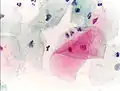

Normal endocervical cells should be present into the slide, as a proof of a good quality sampling

The cytoplasms of squamous epithelial cells melted out; many Döderlein bacilli can be seen.